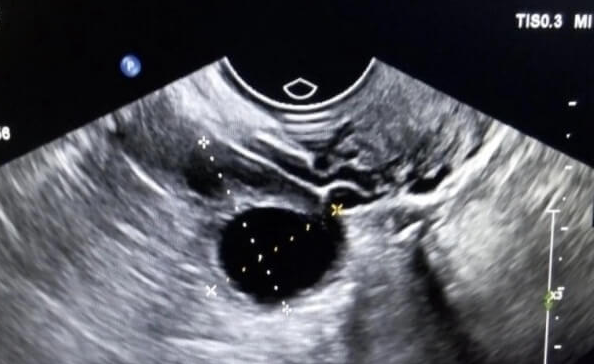

卵巢储备功能是取卵数量的核心决定因素。38岁女性中,卵巢功能正常者基础卵泡数通常在8-12个之间,通过促排卵药物刺激后,可同步发育的卵泡数量可达10-15个。例如,采用长方案促排时,医生通过控制性超排卵技术,可使多个卵泡在10-14天内同步成熟,最终取卵数常维持在10个以上。但若存在早发性卵巢功能不全(POI)或多囊卵巢综合征(PCOS)等疾病,卵泡发育可能呈现两极分化:POI患者因卵泡池缩小,即使加大药物剂量也难以获得足够卵泡;PCOS患者则可能因卵泡过度募集导致卵巢过度刺激综合征(OHSS),反而需要减少促排药物剂量。

除卵巢功能外,促排卵方案的选择、药物反应性及代谢速度等因素也会显著影响取卵数。临床数据显示,38岁女性采用拮抗剂方案时,平均取卵数为6-8个;而微刺激方案因用药剂量低,取卵数通常在3-5个之间。值得注意的是,部分卵巢功能良好的女性可能因药物代谢快,需延长促排周期至14天以上才能达到取卵标准,这类患者最终取卵数常超过12个。